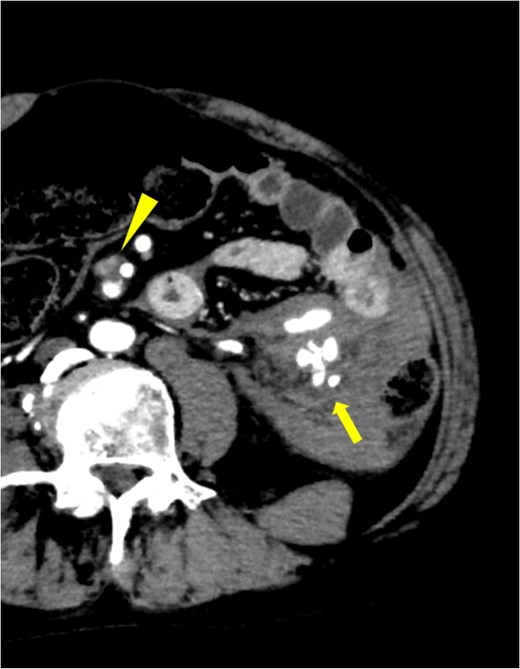

A 53-year-old man with a 21-year history of SLE presented to our emergency department with sudden onset of abdominal pain during defecation. His past medical history included SLE, deep venous thrombosis (DVT), refractory symptomatic epilepsy, and neurogenic bladder. His medications included predonine (used for 21 years), warfarin (for DVT), and antiepileptic drugs. His blood pressure was 100/60 mmHg, and his heart rate was 140 bpm. Physical examination revealed abdominal distention, strong spontaneous pain, and tenderness in the left side of the abdomen. Furthermore, the patient had rebound tenderness in the same region. Laboratory examination revealed severe anemia (Hb 8.4 g/dL) and elevated inflammatory markers (C-reactive protein: 7.90 mg/dL). Both prothrombin time (PT) and activated partial thromboplastin time (APTT) were prolonged (PT: 57.8 s, APTT: 71.2 s). Contrast-enhanced computed tomography (CT) of the abdomen revealed an extravasation in the left side of the abdomen, continuous from the inferior mesenteric artery (IMA). In addition, a spindle-shaped dilatation with an internal contrast-deficient area with a maximum diameter of 17 mm, was observed 16 mm peripherally from the origin of the superior mesenteric artery (SMA) (Fig. 1). No areas of contrast failure were observed in the intestinal tract. Emergency laparotomy was performed on the same day due to patient’s declining condition. A large amount of bloody ascites and clots were present in the abdominal cavity. A hematoma, ⁓10 cm in size was found in the mesentery of the splenic flexure of the colon and was considered the source of hemorrhage. No other sources of hemorrhage were found. Hemostasis was achieved through compression. Although we considered closing the abdomen and performing interventional radiology for hemostasis, there was a risk of ischemic necrosis of the descending colon after embolization. Therefore, we decided to excise the descending colon, including the hematoma. The intestinal tract and mesentery from the splenic flexure to the middle of the descending colon were resected to remove all the hematoma. Due to significant intestinal edema caused by aggressive hydration, we could not close the abdomen and opted for open abdominal management without intestinal anastomosis. A second look surgery was performed 2 days after the initial surgery. The risk of anastomotic leak was considered high based on the patient’s condition, so descending colostomy was performed. The patient was discharged 28 days after the initial surgery without any postoperative complications. The resected descending colon had a large, bulging hematoma on the serosal side, measuring 9 × 6 cm. Histopathological examination of the resected colon revealed mild but diffuse dilatation of a major branch of the IMA running parallel to the bowel, which was embedded within the hematoma. The structure of the dilated artery was completely destroyed, leaving only the fibrin layer. Inflammatory infiltrate, including neutrophils, was observed around the affected vessels (Fig. 2). The bowel wall was intact. Other than SLE, the patient had no comorbidities that could cause the formation of multiple aneurysms in the SMA and IMA. Therefore, this aneurysm was suspected to be caused by SLE.

Extravasation continuous from IMA was observed (solid arrow), and active bleeding from the same region was suspected. Aneurysm with internal thrombus was observed near the origin of SMA (arrowhead).